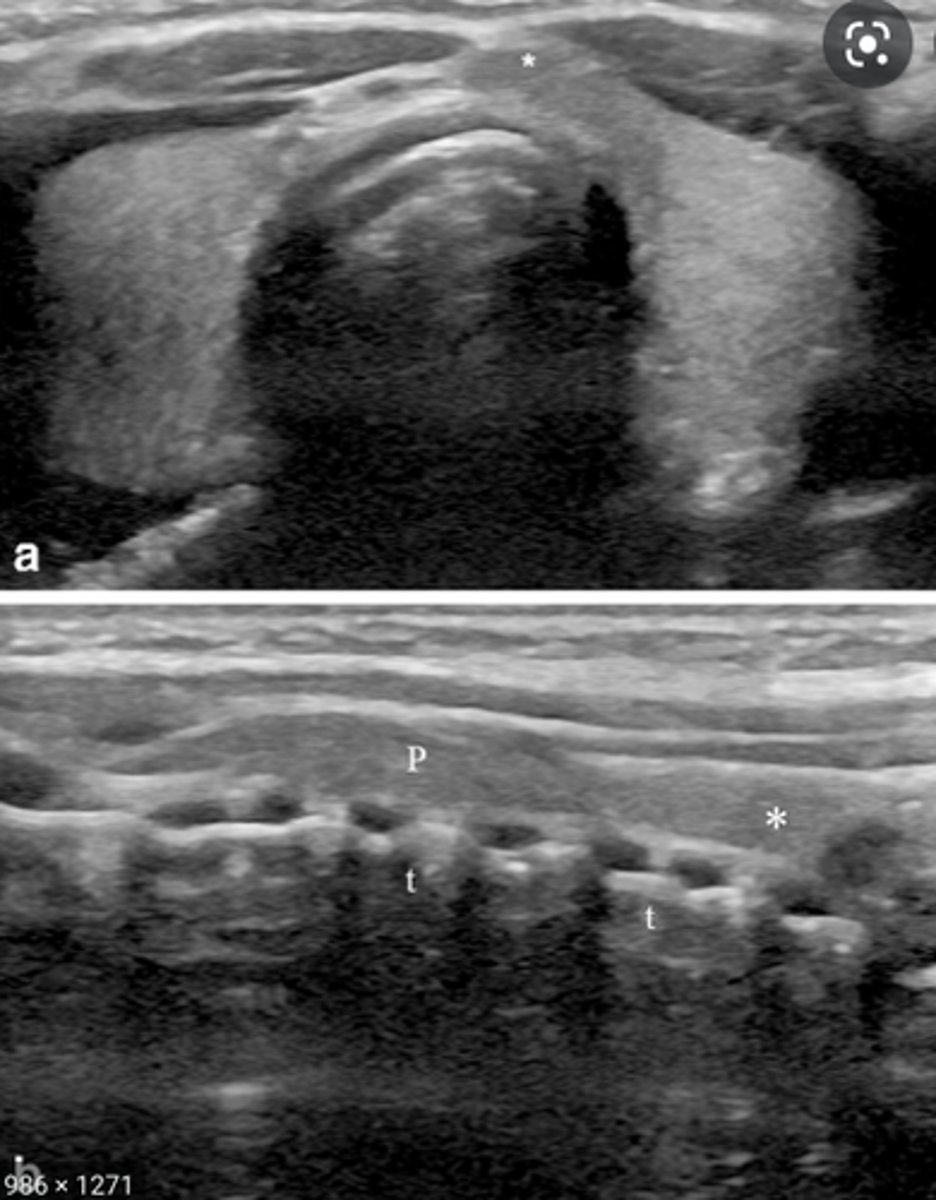

Anatomy of the Thyroid Glands:

-Largest _____ gland in the human body

-Divided into the right and left lobes with a connecting _____

-_____ lobe is usually larger than the _____

-Isthmus connects the _____ third of the thyroid lobes

-Consists of follicles, connective tissue, nerves, lymphatics, and stroma

-Covered by two layers of _____

-Largest endocrine gland in the human body

-Divided into the right and left lobes with a connecting isthmus

-Right lobe is usually larger than the left

-Isthmus connects the lower third of the thyroid lobes

-Covered by two layers of connective tissue

Congenital Anomalies - Pyramidal Lobe:

-Third lobe arising from the _____ portion of the _____

-Ascends to the level of the _____

-Appears in _____% of patients

-Begins to _____ in adulthood

-Appears _____echoic to the normal thyroid gland

-Third lobe arising from the superior portion of the isthmus

-Ascends to the level of the hyoid bone

-Appears in 10-40% of patients

-Begins to atrophy in adulthood

-Appears isoechoic to the normal thyroid gland

Sonographic Appearance:

-Thyroid lobes and isthmus appear as ____geneous solid structures demonstrating a medium-gray echo pattern with a surrounding thin ____echoic line

-Thyroid lobes and isthmus appear as homogeneous solid structures demonstrating a medium-gray echo pattern with a surrounding thin hyperechoic line